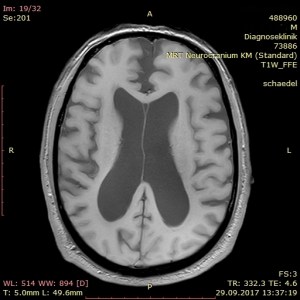

Dieser Tage erhielt ich einen erschreckenden Einblick in das Ausmaß der Zerstörung Meinerselbst durch Vater und Mutter, die beiden Mörder meiner Seele. Auf der diagnostischen Suche nach der Ursache für meinen Schwankschwindel wurde auch mein Schädel fixiert und per MRT durchleuchtet. Nach der 25minütigen Prozedur in der Röhre traf ich den Radiologen vor dem Bildschirm und sah mir scheibchenweise ins Gehirn. Der Arzt war sichtlich betroffen über die auffällige Atrophie meines Gehirns. Er zeigte mir die ungewöhnlich ausgedehnten Ventrikel, sprich Hohlräume, an den Seiten und im Innenraum meines Brägens. Er fragte nach möglichen Erkrankungen wie Diabetes und Bluthochdruck. Ich verneinte und erwähnte meine PTBS. Er erkundigte sich nach der Ursache, ich verstand die Frage akustisch nicht, meine Frau antwortete für mich: sexueller Missbrauch und Misshandlung durch die Eltern. Nun kam zu seiner Betroffenheit noch ein tieftrauriger Zug, und er erklärte mir, dass Missbrauch und Misshandlung derlei tiefe und bleibende Spuren im Gehirn hinterlassen. Angesichts meiner geistigen Präsenz zeigte er zudem über die strukturelle Regenerationsfähigkeit des Gehirns Erstaunen. – Später sah ich im Internet das „Schalenhirn“ eines Mathematikers mit einem IQ von 126, das nur geschätzte 100 g Masse besaß (siehe hier).

In meinem Therapietagebuch notierte ich dazu trocken: „Neben dieser Diagnose: keine Blutungen, keine Aneurysmata, keine Tumore oder Metastasen. Nur ein weiterer Ausschluss auf der Diagnose zum psychogenen Schwankschwindel. Die Hirnatrophie selbst ist nur ein Sachverhalt des Missbrauchs, man kann auch mit einem „Resthirn“ gescheit und sinnenfroh überleben.“

Als Hörbeispiel meiner nachhaltigen Schädigung von Angst und PTBS habe ich abschließend ein Video des Bordun Orchesters eingebettet. Die Bilder in diesem Beitrag kehren mein sichtbar zerstörtes Inneres, sprich mein Gehirn, nach außen.

kurz zu ihren schnittaufnahmen vom kopf. ich bin kein fachmann und kann damit nicht viel anfangen, obwohl ich vor vielen jahre einem oberarzt erklären musste, wir er mit schnittaufnahmen umzugehen hat. er sagte über die aufnahmen unseres jüngsten den ermutigenden satz: aber der hat ja kein gehirn. – ich habs ihm dann gezeigt. unser jüngstes kind, ein adoptivkind, kam mit einem hirnschaden zur welt, dazu gehörte der hydrozephalus (wasserkopf). ganz beiläufig hatte ich im psychologie-studium gelernt, dass man auch mit hydrozephalus beachtliche leistungen erbringen kann.